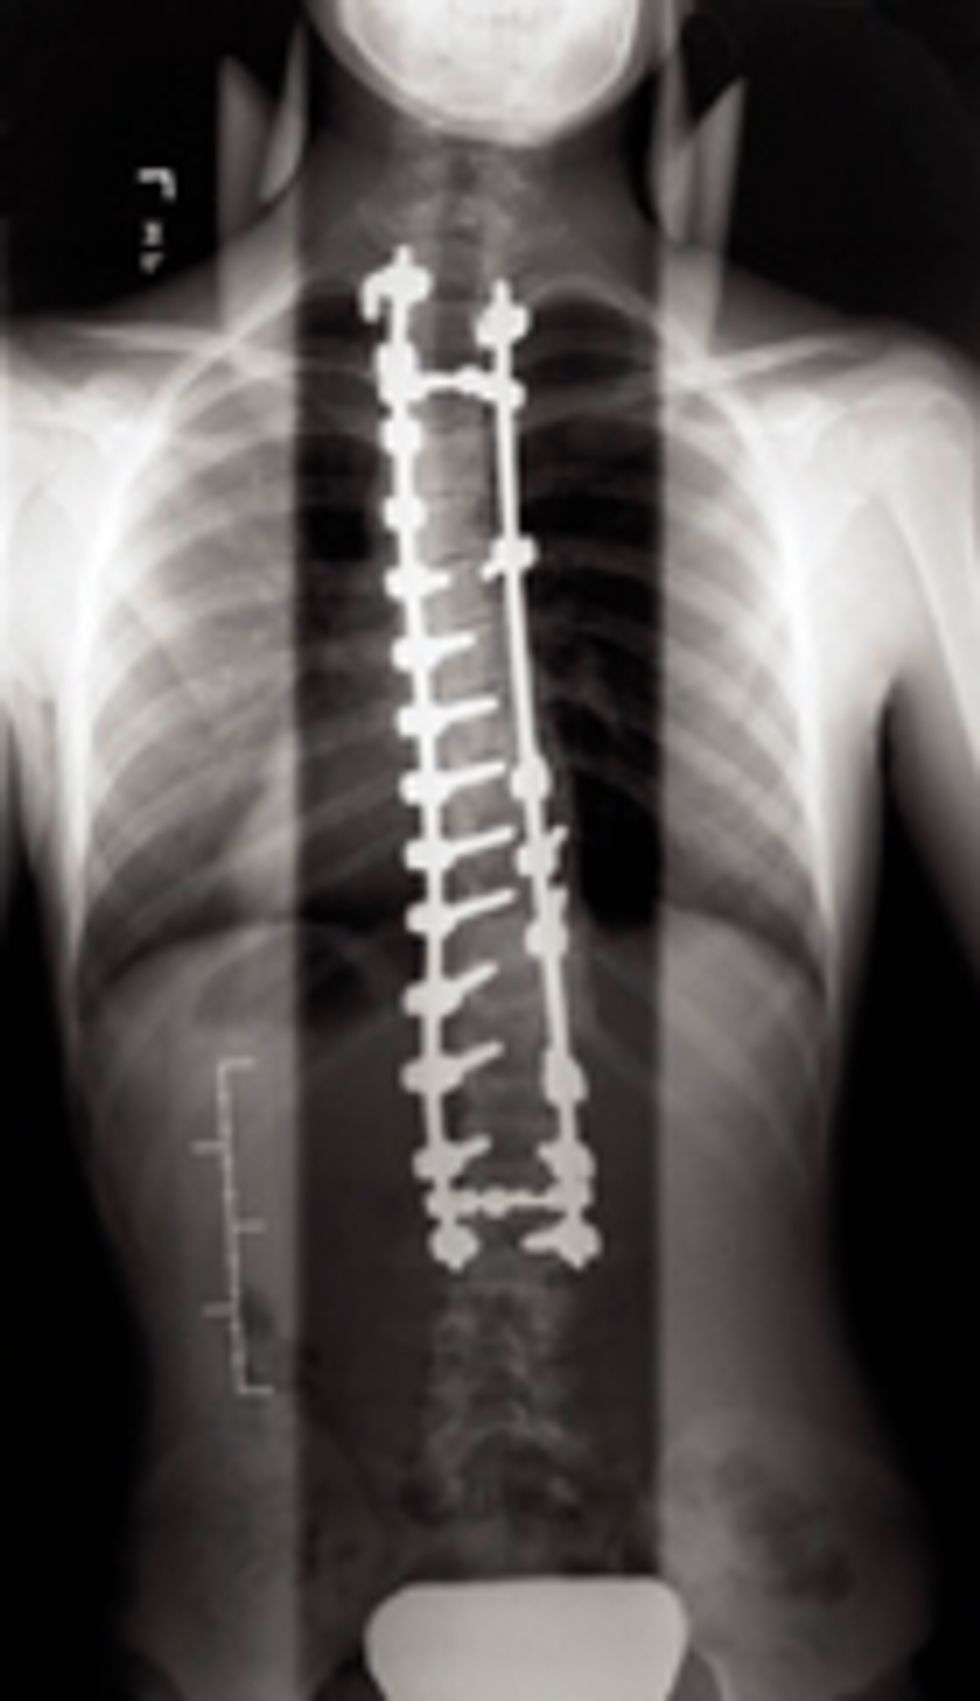

The surgery took eight hours, and halfway through they had me wiggle my toes to make sure I wasn't paralyzed. The placed screws, hooks, and rods as well as fused my spine. I had a S curve(Meaning my spine looked like an S) so they had to fuse my entire spine. They also broke all of my ribs on my right side and corrected them because they were deformed from the severe Scoliosis.

This is kind of what my spine looks like in the sense of the screws, rods, and hooks ) Mine do go the entire length of my spine though)